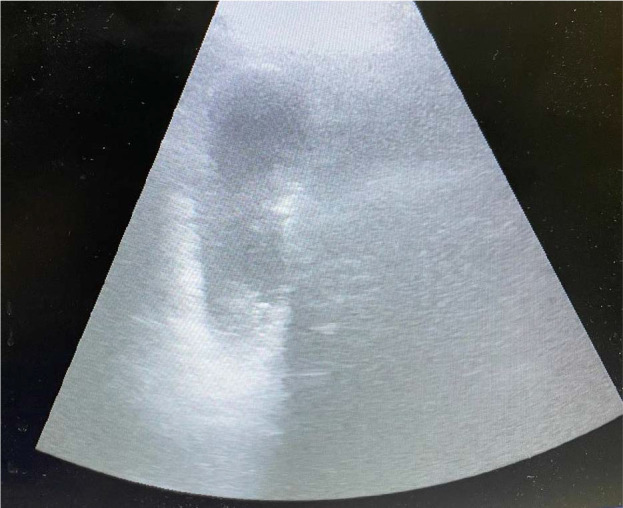

Case presentation: In this report, we describe the case of a 66-year-old patient who presented to the emergency department with a clinical picture dominated by fever, an altered general condition, abdominal pain in the right hypochondrium, nausea, and repeated vomiting. Acute calculous cholecystitis was diagnosed based on clinical, laboratory, and imaging findings. During preoperative preparation, the patient exhibited signs of liver and renal failure with severe coagulation disorders. Obstructive jaundice was excluded after performing an abdominal ultrasound and computed tomography scan. The suspicion of leptospirosis was then raised, and appropriate treatment for the infection was initiated. The acute cholecystitis symptoms went into remission, and the patient had a favorable outcome. Surgery was postponed until the infection was treated entirely, and a re-evaluation of the patient's condition was conducted six-week later.